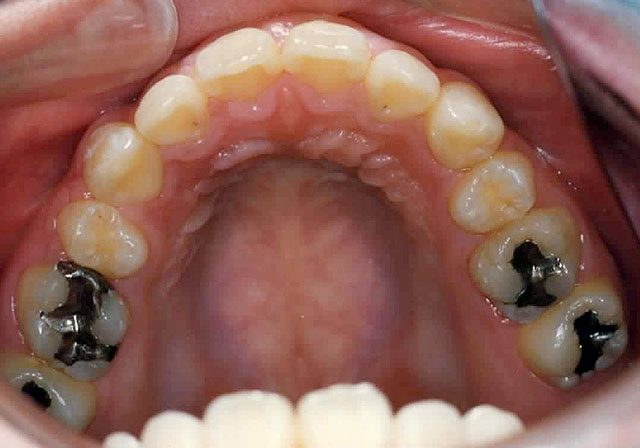

Before

顎の大きさに対して歯の幅の合計が大きすぎるため通常、第1小臼歯を抜歯します。

マルチブラケット法による矯正治療を開始。